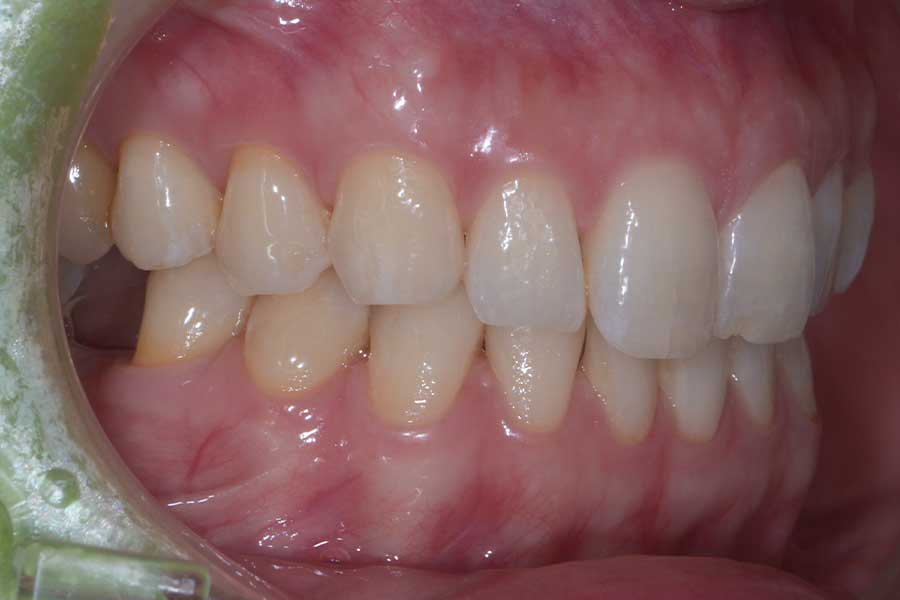

治療後

主訴 インプラント治療前にブラックトライアングルを消したい

治療内容 上下顎ラビアル矯正(表側矯正)

治療に伴うリスク 後戻り